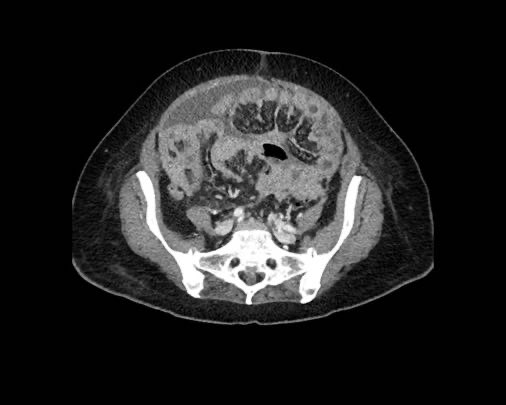

Cuộn xem ảnh CT

Ca lâm sàng 1

Cuộn qua các lát cắt.

Bạn có thể phát hiện tất cả các tổn thương cấy ghép phúc mạc không?

Bệnh nhân này đã được phẫu thuật và toàn bộ phúc mạc được ghi nhận phủ kín bởi các tổn thương u dạng kê.